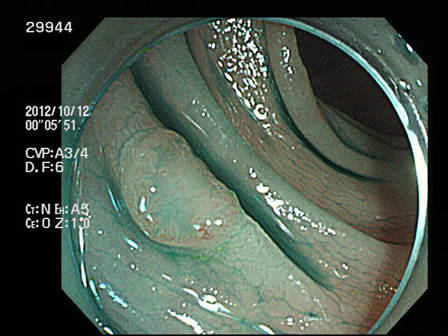

29901 29904 29905 29906 29907 29908 29909 29913 29915 29917 29918 29921 29925 29926 29927 29928 29930 29934 29936 29938 29939 29940 29941 29942 29943 29944 29945 29947 29948 29949 29955 29959 29961 29962 29965 29968 29972 29975 29979 29980 29981 29983 29985 29986 29987 29989 29993 29996 29998 29999・・・・・・・の50名

上記100名より抽出した平坦・陥凹型腺腫(=癌化の危険が高いが見落としやすい病変)の内視鏡写真